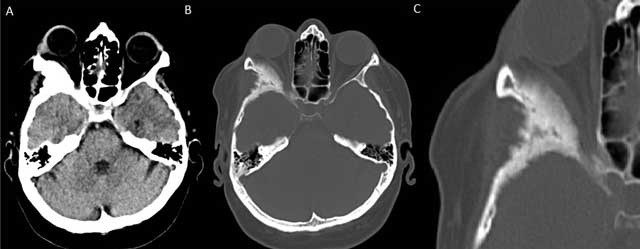

Figure 1

Non-contrast enhanced axial CT of the brain with soft tissue (A) and bony window reconstructions (B) shows an expansile sclerotic lesion in the right sphenoid wing. Involvement of the right lateral orbital wall leads to narrowing of the orbital space and secondary proptosis. A zoomed-in view in bony window (C) shows the irregularly marginated sclerotic expansion of the right lateral orbital wall in more detail.